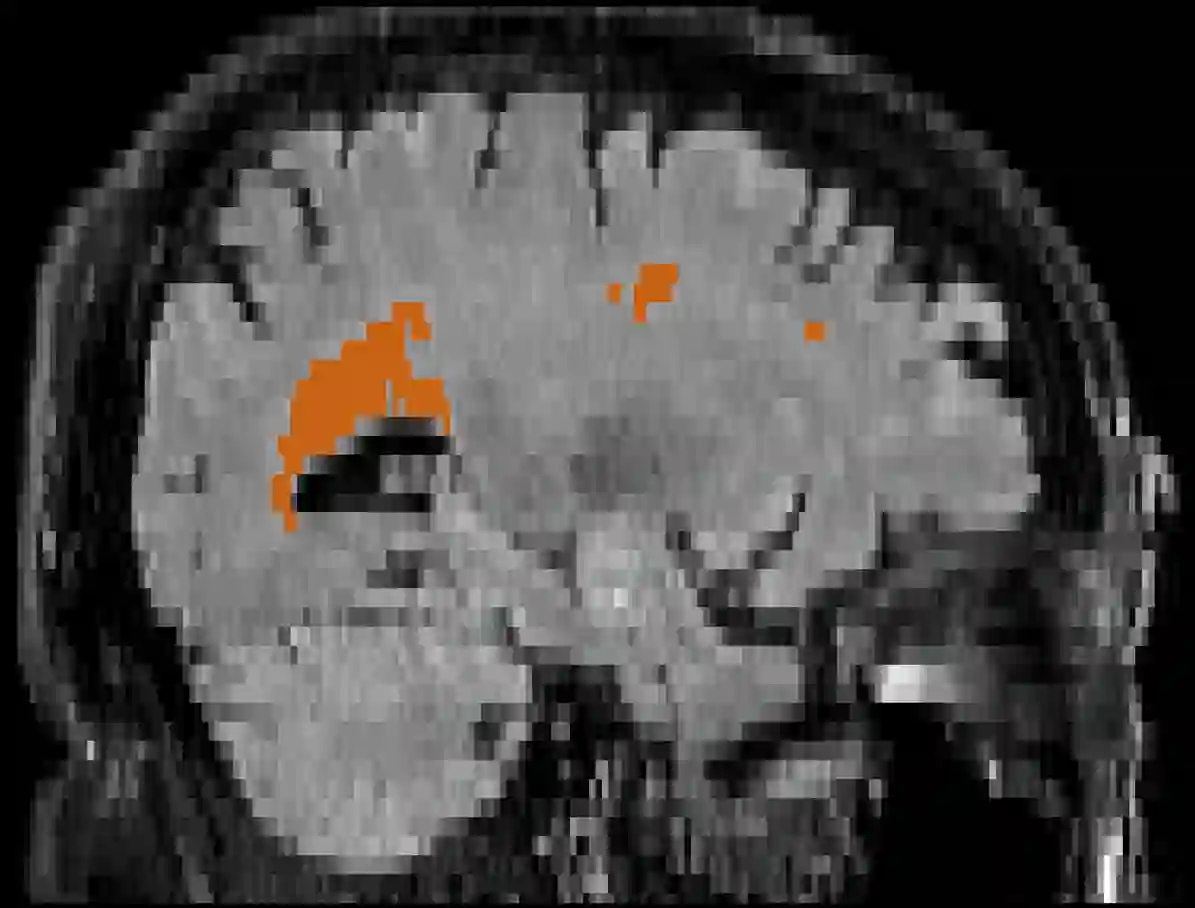

Brain atrophy and white matter hyperintensity (WMH) are critical neuroimaging features for ascertaining brain injury in cerebrovascular disease and multiple sclerosis. Automated segmentation and quantification is desirable but existing methods require high-resolution MRI with good signal-to-noise ratio (SNR). This precludes application to clinical and low-field portable MRI (pMRI) scans, thus hampering large-scale tracking of atrophy and WMH progression, especially in underserved areas where pMRI has huge potential. Here we present a method that segments white matter hyperintensity and 36 brain regions from scans of any resolution and contrast (including pMRI) without retraining. We show results on six public datasets and on a private dataset with paired high- and low-field scans (3T and 64mT), where we attain strong correlation between the WMH ($\rho$=.85) and hippocampal volumes (r=.89) estimated at both fields. Our method is publicly available as part of FreeSurfer, at: http://surfer.nmr.mgh.harvard.edu/fswiki/WMH-SynthSeg.